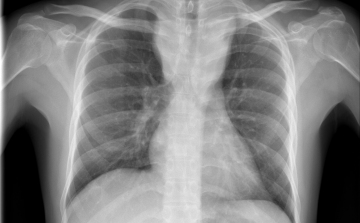

Először találtak élő emberek tüdeje mélyén műanyag mikroszemcséket

Először találtak élő emberek tüdeje mélyén műanyag mikroszemcséket: műtéten átesett 13 páciens közül 11-ben fedezték fel a részecskéket.